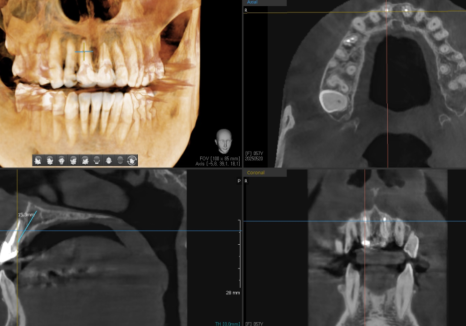

CT로 정확한 위치

확인 후 식립

잇몸 까매짐 원인,증상,치료 방법

250520

앞니는 심미적으로

가장 중요한 부위입니다.

어금니도 물론 중요하지만,

앞니는 식립 각도와 깊이가

조금만 어긋나도

최종 보철이 부자연스럽게 보일 수 있고

심할 경우 잘못된 식립 각도로 인해

임플란트가 파절될 수도 있습니다.

그래서 저는 식립 전 CT로

정밀하게 계획을 세우고

식립 후에도 촬영해서 의도한 대로

정확하게 들어갔는지 한 번 더 확인합니다.

이런 과정이 번거로워 보일 수 있지만,

환자분께 오래 쓰실 수 있는 결과를

드리기 위해 꼭 필요한 단계라고 생각해서

더욱 꼼꼼하게 확인합니다.^^